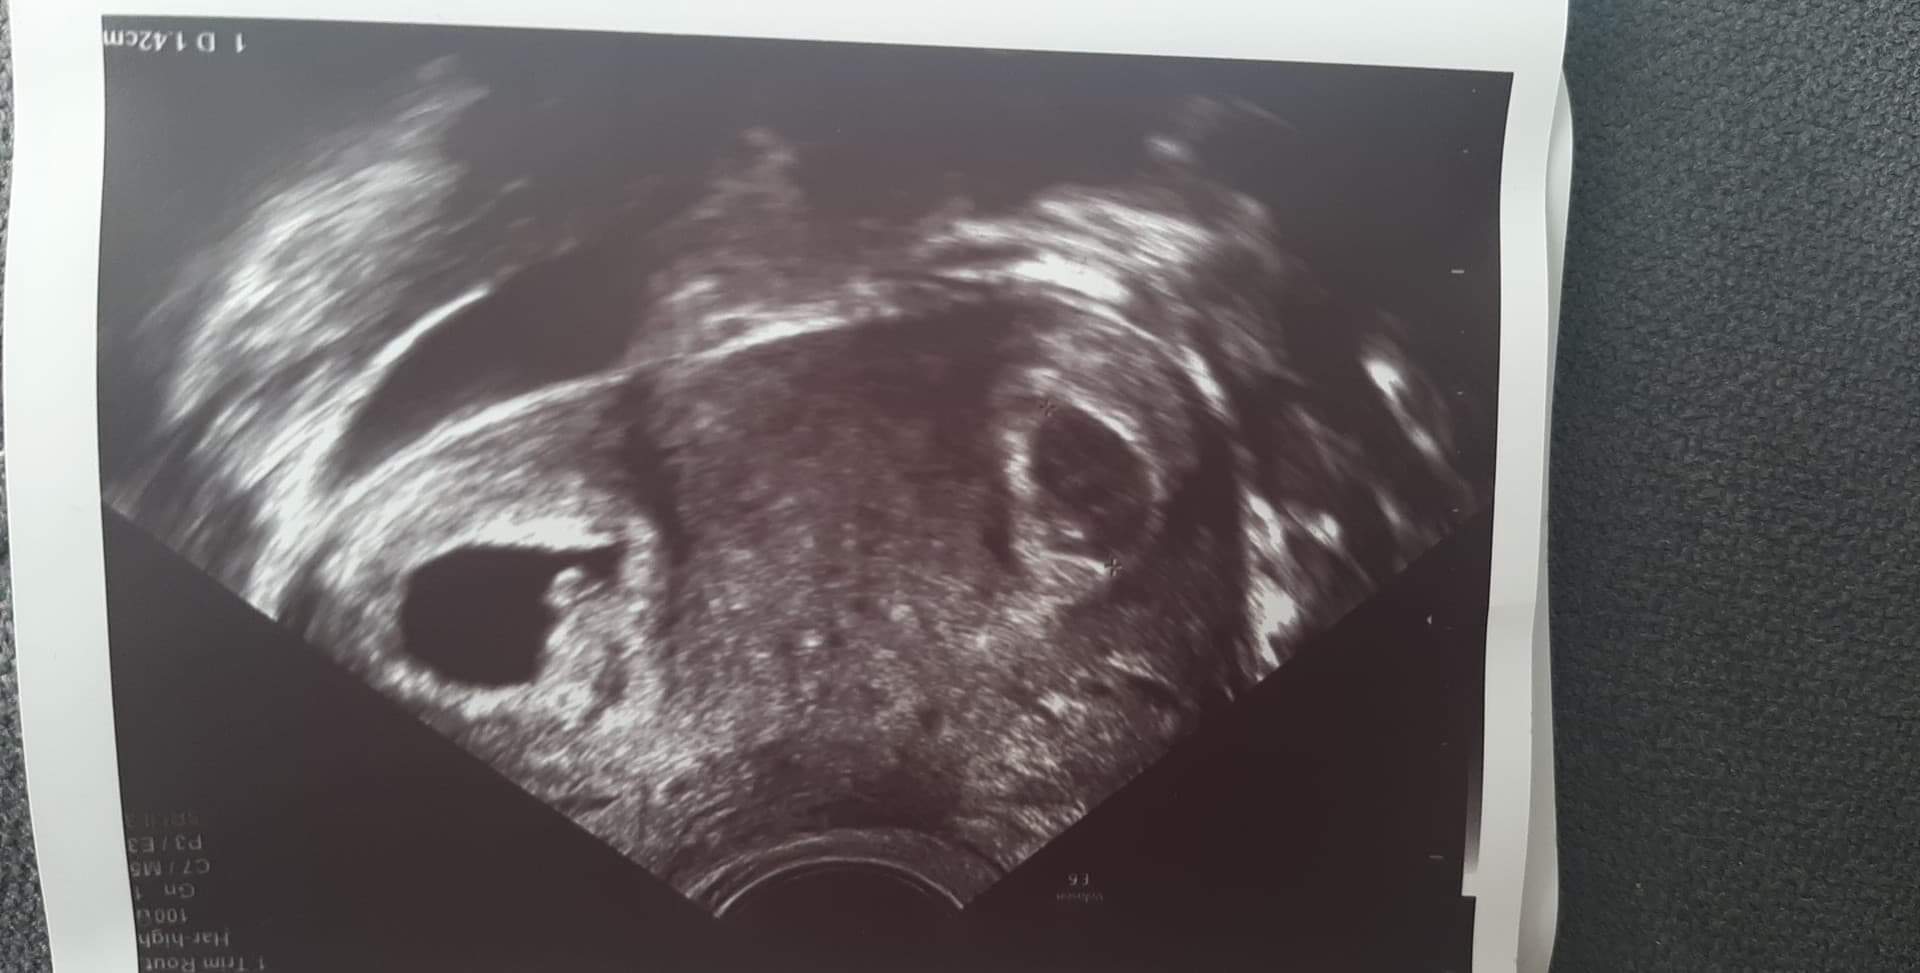

byłaś na naturalnym cyklu?Dziewczyny jestem po wizycie... wszystko ok, zarodek rośnie, bije serduszko, ale.... mialam podany 1 zarodek, a pojawił się 2 pęcherzyk!!! Jest narazie maleńki i niewiadomo czy z zarodkiem.... Boże, stresuje sie teraz, zeby temu pierwszemu nie zaszkodził